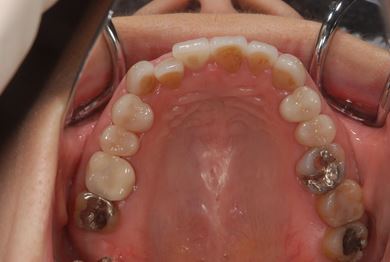

セラミックの症例写真 SHINBI

セラミック治療+ラミネートベニア治療

| 主訴 | 虫歯を白い詰め物で治療したい。全体的に歯の色が気になるので、ホワイトニングをしたい。ホワイトニングの効果がなければ、セラミック治療を受けたい。 | ||||||||||||||||||||||||||||||||

| 治療方針 | セラミック治療にて、審美的回復を行う。 | ||||||||||||||||||||||||||||||||

| 治療内容 | ジルコニアオールセラミッククラウン1本(オールセラミック用土台1本)、オールセラミッククラウン9本(オールセラミック用土台1本)、オールセラミックラミネートベニア11本 | ||||||||||||||||||||||||||||||||

| 総治療費 | 2,893,275円 | ||||||||||||||||||||||||||||||||

| 治療期間 | 10ヶ月 |